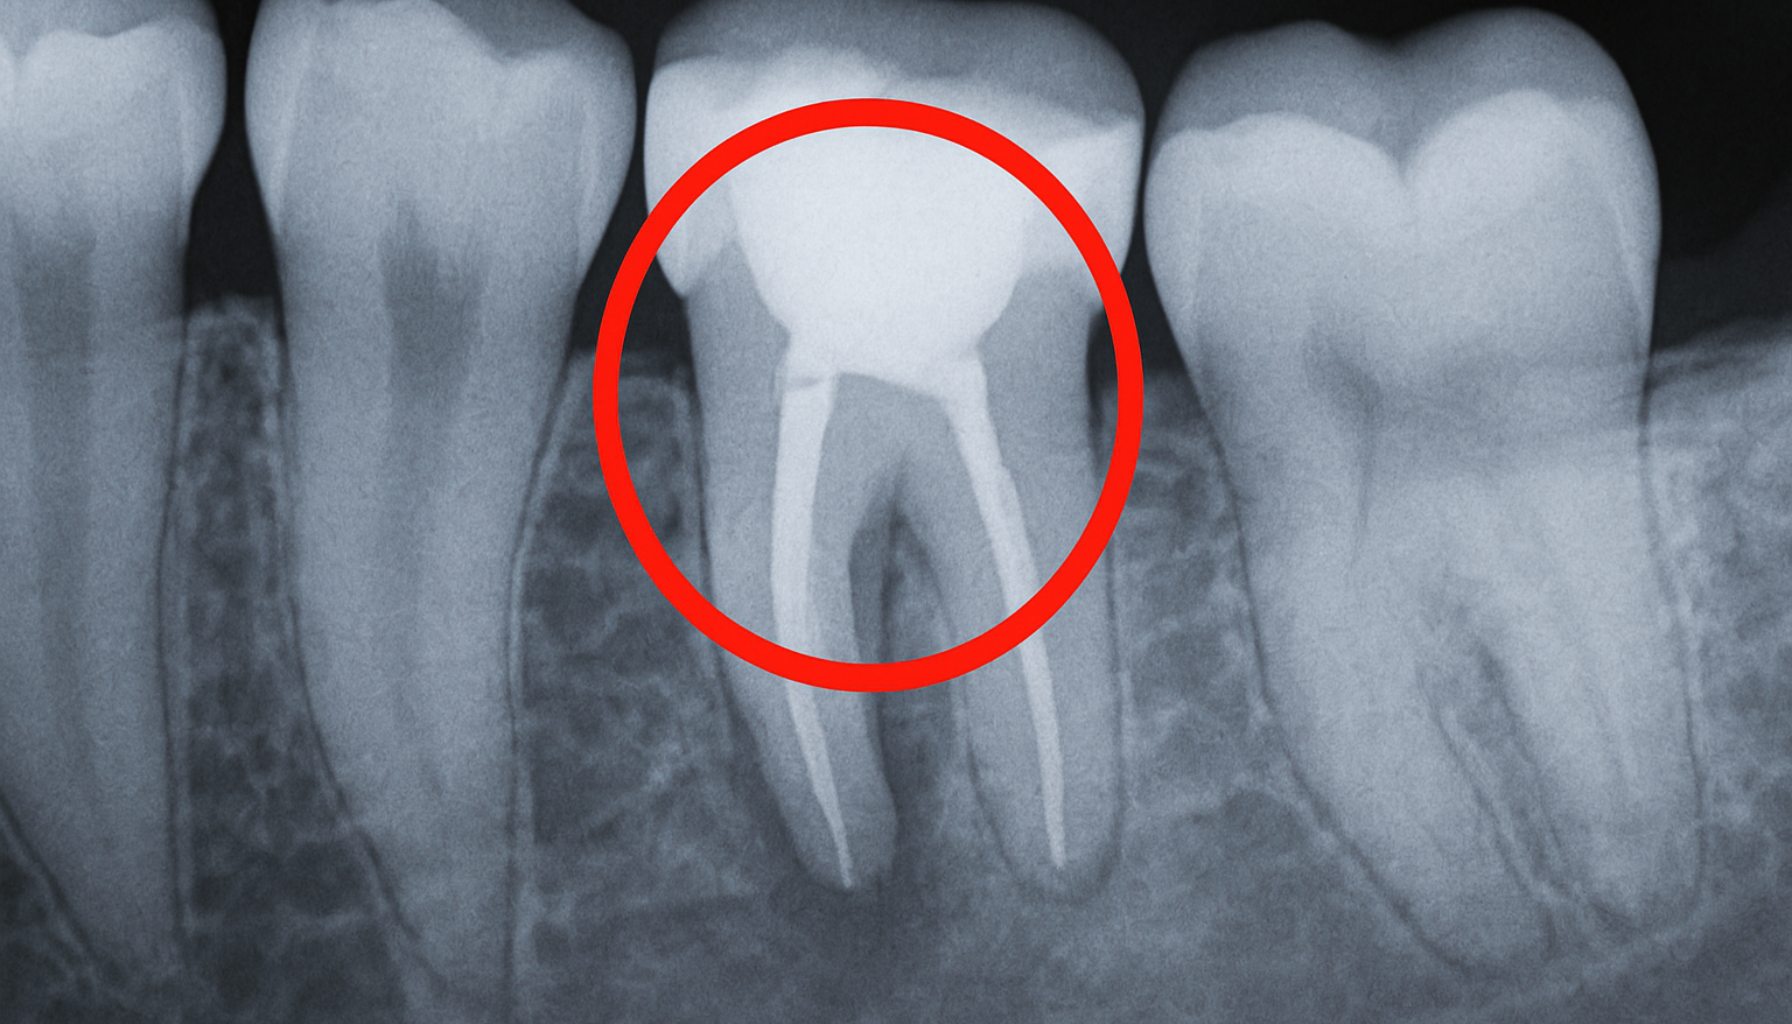

Prosedyren for å sette en tann på stift skjer i flere trinn. Først vil tannlegen gjøre en grundig vurdering av tannen for å sikre at den er egnet for behandling. Dette kan innebære røntgenbilder for å vurdere rotens tilstand. Deretter vil tannlegen fjerne eventuelle rester av infisert eller dødt vev i rotkanalen, før de fyller den med et spesialmateriale som tetter kanalen.

Den brukes når store deler av tannen er ødelagt på grunn av hull, skade eller tidligere behandling – og det ikke er nok igjen av tannen til å feste en vanlig krone. - Rotfylling er et krav:

Før stiften kan settes inn, må tannen være rotfylt. Det er viktig at rotfyllingen er tett og stabil for at behandlingen skal lykkes. - Slik fungerer stiften: